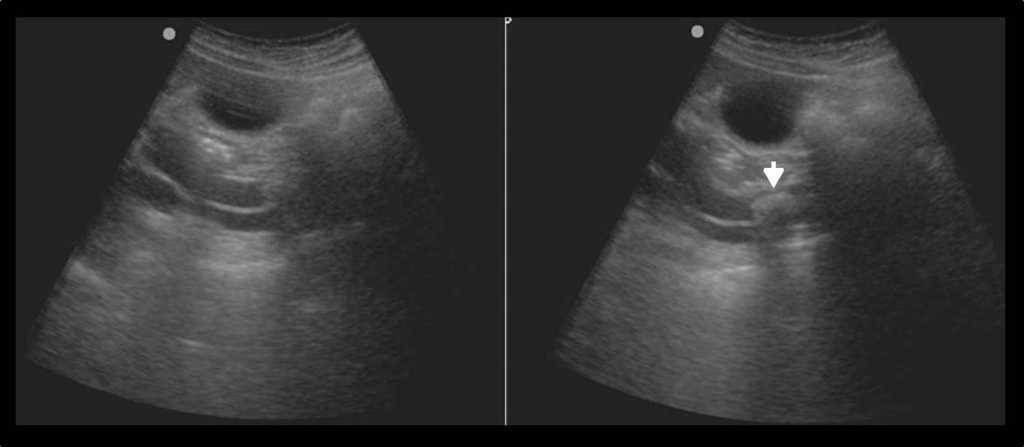

La experiencia demuestra que en situaciones de riesgo de vida (p. ej. politraumatismos), la ecograf??a FAST (Foccused Assesment Sonography for Trauma) es una herramienta sumamente ??til para el diagn??stico de l??quido libre abdominal, dado que visualiza la lesi??n en el ??rgano que lo origin?? (fig. 20). Asimismo, permite evaluar los fondos de los sacos pleurales, el pericardio e, incluso, el retroperitoneo24.